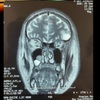

A

How well did you know this?